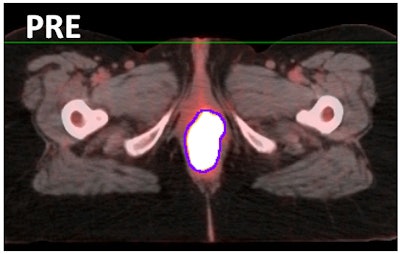

The study included 13 women (median age, 63 years) who had confirmed vulvar cancer ranging from stage IB to stage IVB. All of the subjects had pre- and post-treatment PET/CT scans between 2007 and 2015. The researchers excluded patients who had surgical resection or palliative radiation, as well as women with melanoma or those who had incomplete medical records.

Natesan and colleagues conducted a quantitative analysis, which included maximum (SUVmax), mean (SUVmean), and median (SUVmedian) standardized uptake values, along with a qualitative visual PET analysis to determine complete metabolic response, partial metabolic response, or progression of disease.

Based on the scans, seven patients were found to have a complete metabolic response to treatment, while the other six women had either a partial response or disease progression.